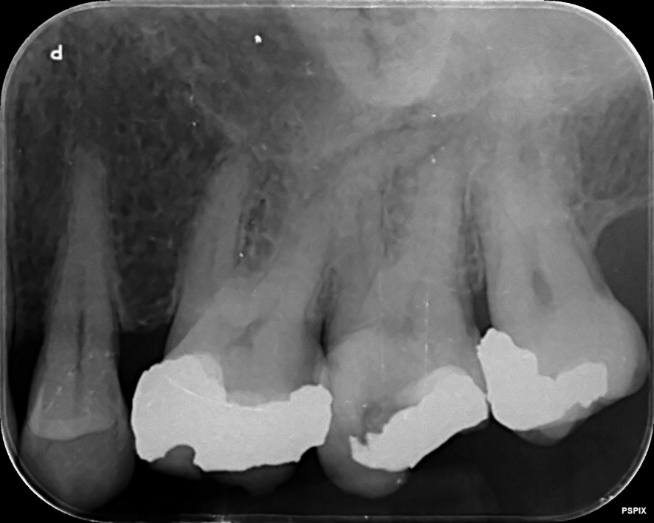

Upper Premolar and Molar root canal treatment and restoration